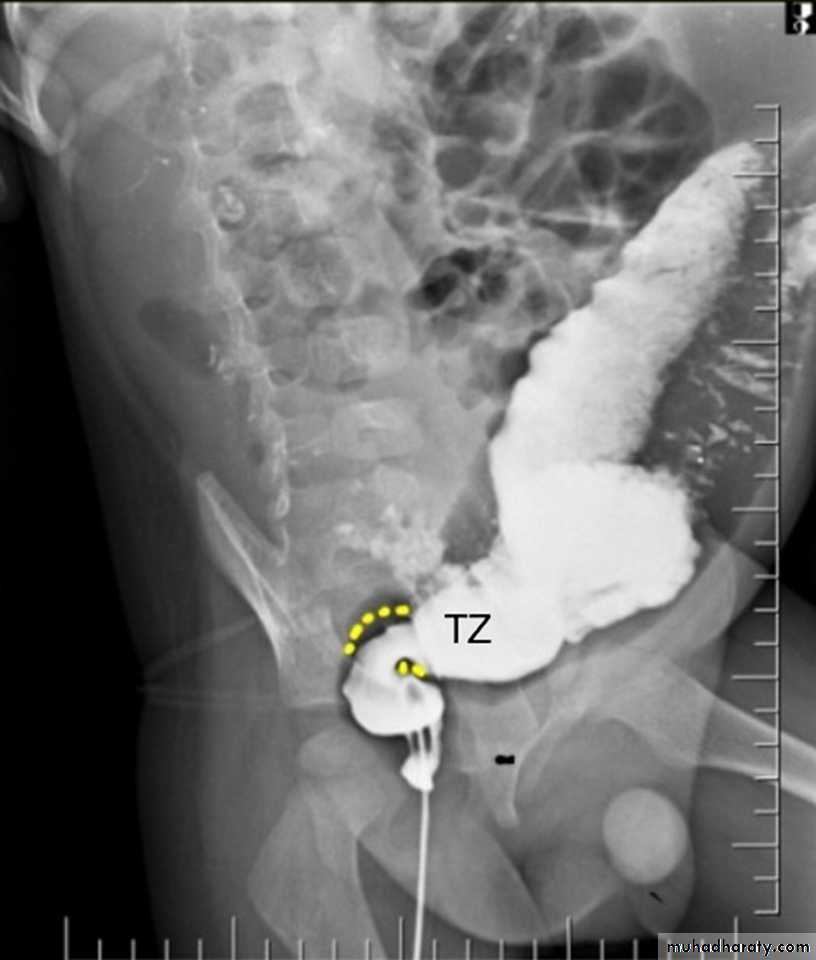

Radiological features of toxic megacolon :

• The colon (typically transverse colon) becomes dilated to at least 6 cm (usually greater). There is additional loss of haustral markings

Toxic megacolon

toxic mega colon